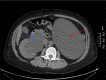

Ureteric strictures can be caused by traumatic pelvic surgery, urolithiasis and instrumentation. There are various treatment options for ureteric stricture, including laparoscopic ureteric reimplantation. A 56-year-old female with a history of chronic left pelviureteric junction obstruction presented with urosepsis secondary to right-sided urolithiasis. The patient had a left nephrectomy and developed right-sided ureteric stricture following repeated ureteroscopy to manage her stone disease. The treatment with ureteric stenting was unsuccessful. Here we present a case on the feasibility of laparoscopic reimplantation for ureteric stricture in a solitary kidney to preserve renal function and avoid further ureteroscopy or nephrostomies.